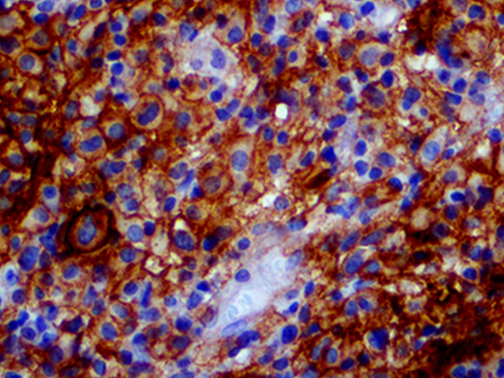

It is the ICU physician who is most likely to witness one of the deadliest manifestations of the abnormal immunological response, the cytokine storm syndrome (CSS). This response is also referred to by some as the cytokine release syndrome (CRS). CSS is characterized by continuous activation and expansion of macrophage and lymphocyte populations, which secrete large amounts of cytokines, causing the cytokine storm. This massive cytokine release is akin to hemophagocytic lymphohistiocytosis (HLH) disease, a syndrome characterized by initial unchecked and persistent activation of cytotoxic T lymphocytes and NK cells.